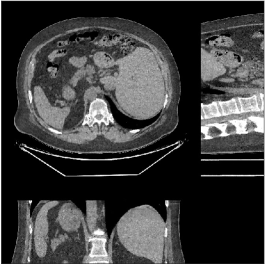

Fig.Β 5 shows the reconstructions and the corresponding error (magnitudes) images (shown for the central axial, sagittal, and coronal planes) for FDK, PWLS-EP, and PWLS-ULTRA () with the patch-based weights. Compared to FDK and PWLS-EP, PWLS-ULTRA significantly improves image quality by reducing noise and preserving structural details (see zoom-ins). Fig.Β 6 shows the RMSE for each axial slice in the PWLS-EP and PWLS-ULTRA (with the weights ) reconstructions. PWLS-ULTRA clearly provides large improvements in RMSE for many slices, with greater improvements near the central slice.

Fig.Β 10 shows the reconstructions (shown for the central axial, sagittal, and coronal planes in the 3D volume) for PWLS-EP and PWLS-ULTRA with patch-based weights () from low-dose abdomen scans. For the sagittal and coronal planes, we show the central out of axial slices. The supplement provides PWLS-EP reconstructions with different regularization strengths. The PWLS-ULTRA reconstructions in Fig.Β 10 have reduced noise as well as higher resolution, better structural details and shaper image edges than the PWLS-EP results. These results are further example of the potential performance of the proposed PWLS-ULTRA method in clinical settings.